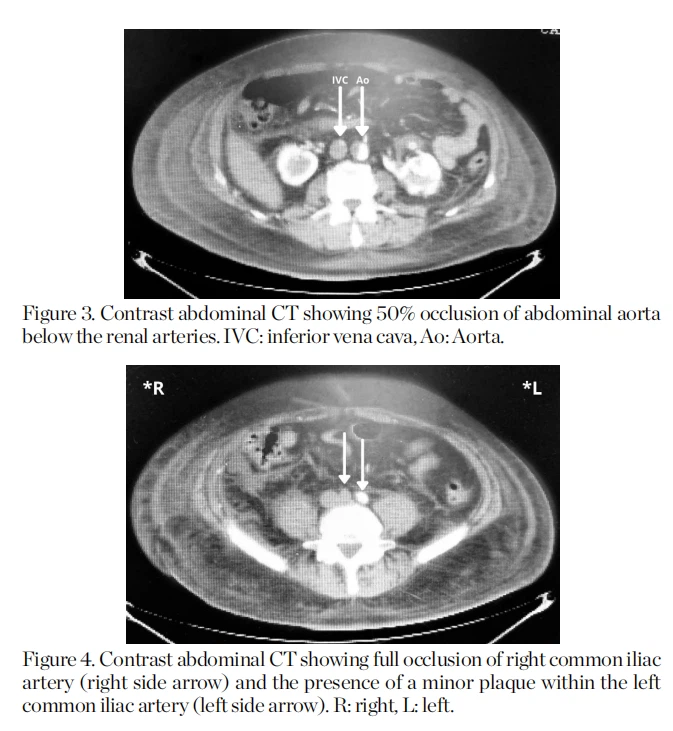

Se consultó al servicio de urología por nefrolitiasis y posible procedimiento de litotricia. Se solicitó tomografía computarizada (TC) abdominal contrastada y angiografía renal, encontrando riñón en herradura y placas ateroscleróticas ocluyendo la luz arterial (Figuras 2, 3 y 4).

Aunque la angiografía convencional se considera el estándar de oro para evaluar la SL, las técnicas de imagen no invasivas pueden identificar la anatomía vascular con gran precisión y se han convertido cada vez más en la técnica de primera elección, especialmente la angiografía por tomografía computarizada (CTA) con reconstrucción tridimensional (3D) que proporciona más información sobre la permeabilidad distal. En nuestro caso, una tomografía computarizada abdominal con contraste fue lo suficientemente clara para demostrar la oclusión vascular, aunque fue accidental. el paciente no pudo ser intervenido por su inestabilidad hemodinámico-respiratoria.

Comorbilidades de los pacientes ycardiovascularlos factores de riesgo pueden acelerar el desarrollo de la enfermedad aterosclerótica.2"1 La claudicación intermitente es el primer indicador de enfermedad arterial oclusiva periférica, pero puede pasar desapercibida durante la anamnesis. En nuestro caso, el uso de la tomografía computarizada abdominal con contraste fue útil para diagnosticar el Síndrome de Leriche .HSK, a pesar de ser una condición rara, predispone a la nefrolitiasis e infecciones del tracto urinario, que son enfermedades comunes. evite pasar por alto síndromes raros y potencialmente mortales.